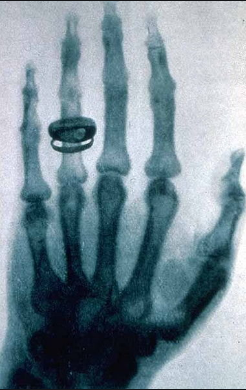

Tre ditë përpara Krishtlindjeve në 1895, Wilhelm Conrad Röntgen realizoi radiografinë e parë të dorës së bashkëshortes së tij. Shoqata Fiziko-Mjekësore e Würzburg ishte e para që dëgjoi për rrezet e reja që mund të depërtonin një regjion anatomik dhe të siguronin një imazh të tij. Në janar 1896, bota u përfshi nga “mania e rrezeve X” dhe Roentgen u shpall zbuluesi i një mrekullie mjekësore.

Fig.1. Radiografia e parë e dorës e realizuar nga Wilhelm Conrad Röntgen.